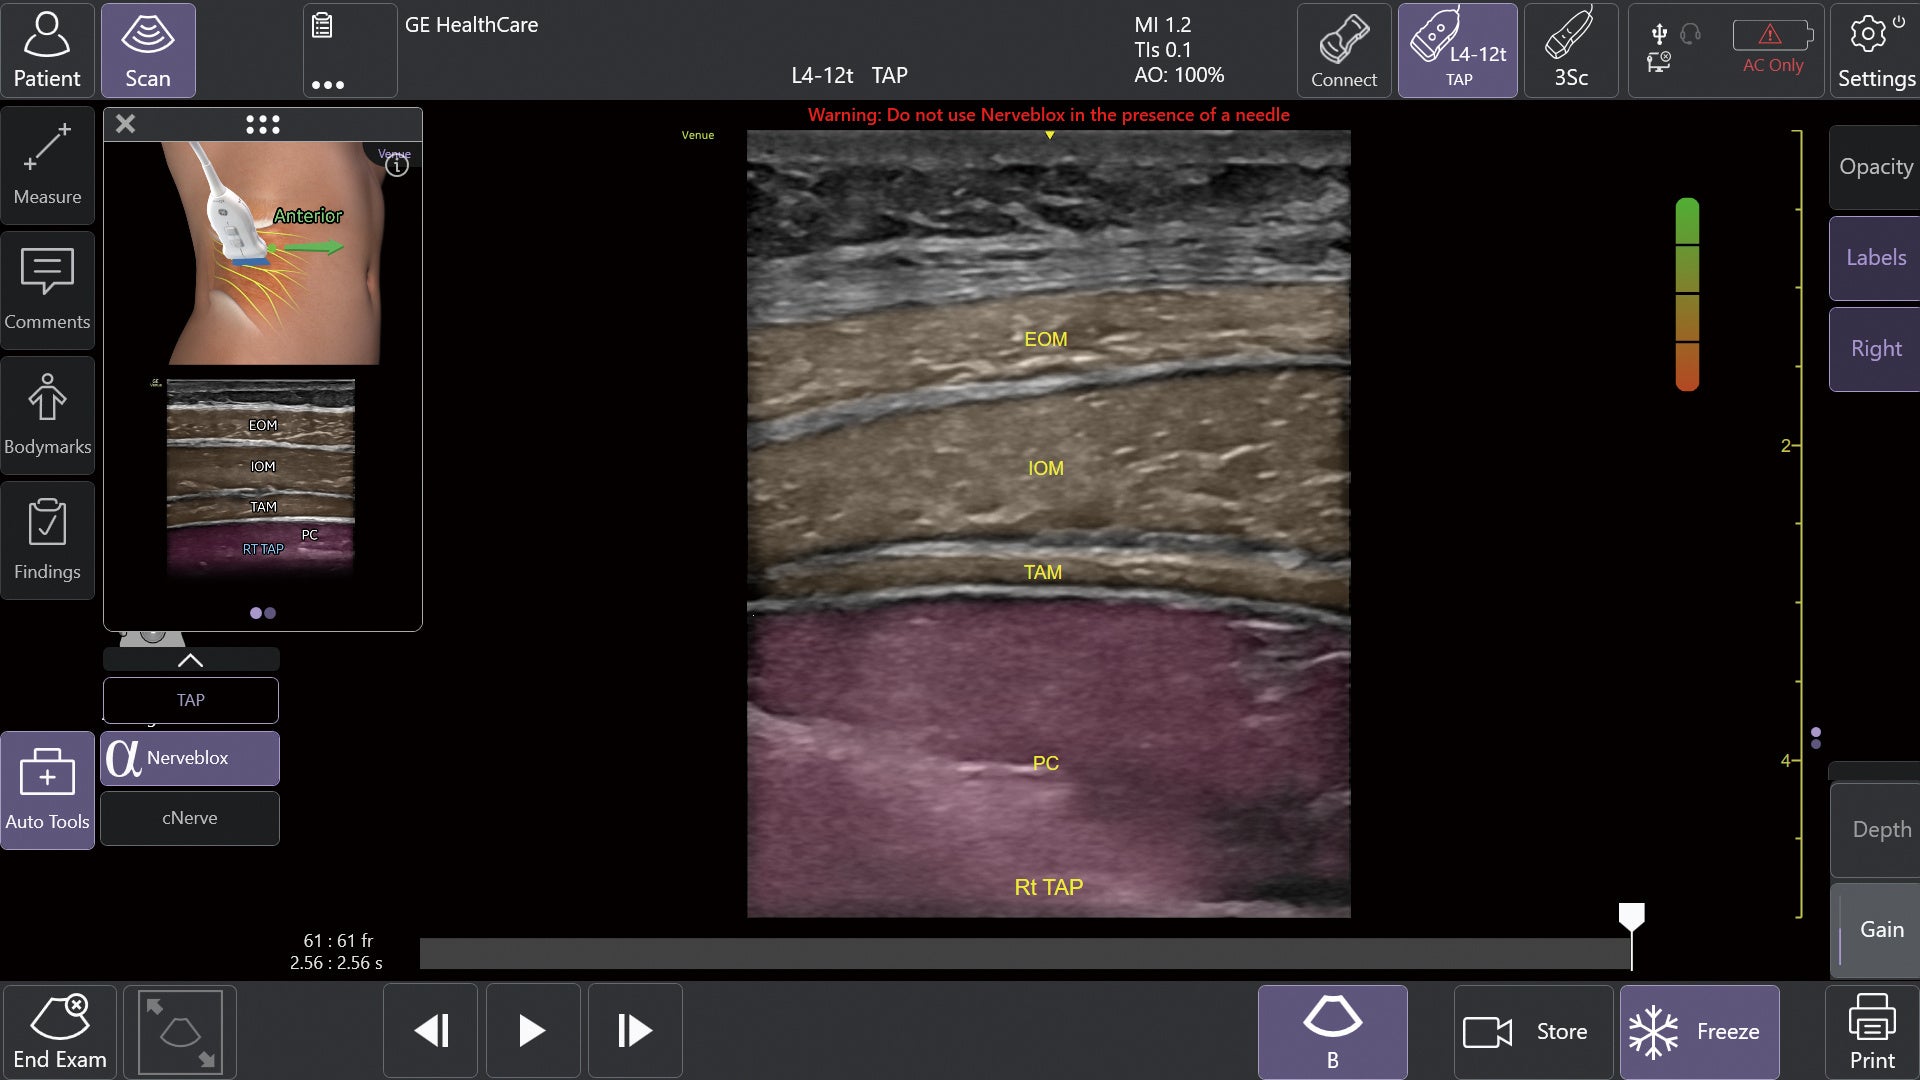

①AIツール Nerveblox(ナーブブロックス)で神経ブロック手技を効果的にサポート

AIを用いて開発されたNervebloxは、区域麻酔に用いられる標準的な12種類の神経ブロック部位に対して、神経および周囲組織(筋肉・血管・骨・筋膜など)をリアルタイムに認識し、ハイライト表示する機能です。

本機能は、画像クオリティを評価するQuality Meter、プローブの向きをガイドするOrientation表示、組織を色分けするカラーオーバーレイ、解剖構造名を示すアナトミカルラベル、理想的なプローブ位置を提示する模式図ガイド等を備え、走査者のエコー経験レベルに依存しない、より安定した神経描出をサポートします。

この機能により、麻酔科、救急科、集中治療科、整形外科など多くの診療科において、神経ブロック時の解剖学的構造の認識や視認性が高まることが期待され、よりスムーズな判断や手技をサポートします。